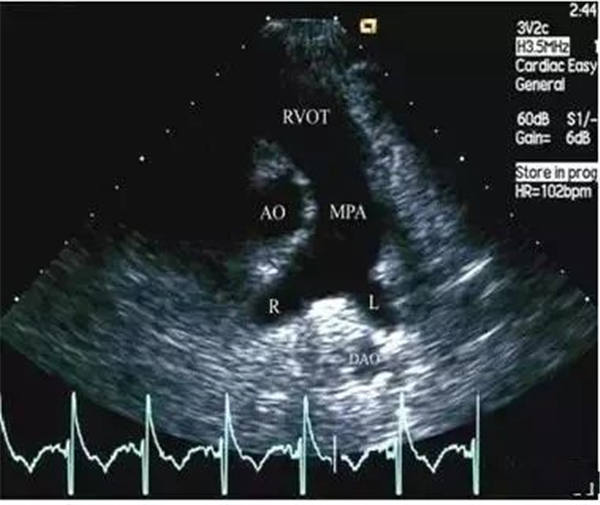

正常的主肺动脉直径(MPA)<30 mm,左肺动脉&右肺动脉( LPA&RPA)<20 mm;而血栓栓塞性肺动脉高压(EPH)患者的MPA>30 mm,LPA&RPA>20 mm;慢性血栓栓塞性肺动脉高压(CTEPH)患者的MPA扩张则更加明显。

正常肺动脉